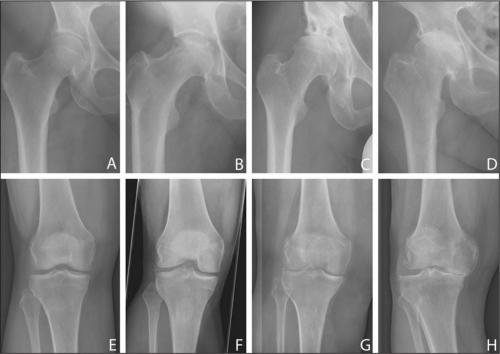

На изображении справа заметно сращение суставной щели.

Гонартроз коленного сустава на рентгене.

Стадии артроза коленного сустава. Обратите внимание на сужение суставной щели.

- гонартроз . Он встречается практически в 50% всех случаев поражения сочленения. Патология развивается очень долго. Среди симптомов этой болезни можно выделить такие: колено не болит в состоянии покоя, однако человеку становится трудно, долго ходить,. Во время движения больной слышит, у него снижается подвижность. Со временем, вследствие изнашивания хряща, расстояние между костными поверхностями уменьшается. При этом появляются, нервы и сосуды сдавливаются, а само колено деформируется;

Все медикаментозные средства эффективны лишь—, но бессильныи IV. Если в патологию вовлечены не только суставы, но и кости, никакой препарат не поможет. В этом случае избавиться от хронических, трудностей при ходьбе, ограниченной подвижности суставов и других неприятных симптомов можно только с помощью операции.